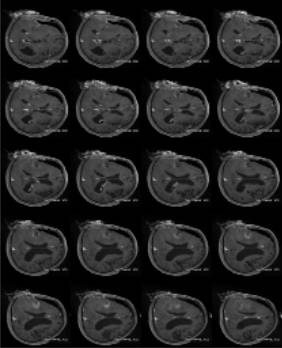

![]() 術中MRI